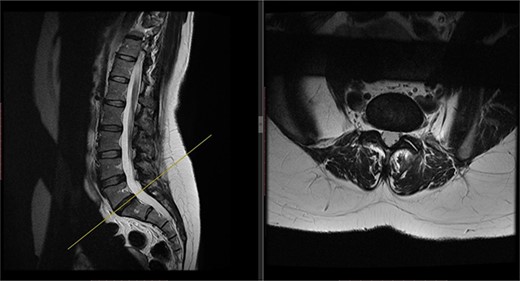

Postoperatively, the patient developed severe radiculopathy down the left leg and required opiates. The patient could not move the left leg and was unable to mobilize. X-rays showed the implants were in position (Fig. 3), but the information from a fresh MRI scan was limited due to metal artefact (Fig. 4). With ongoing, unrelenting pain, she was returned to theatre on the fourth postoperative date, and the wound was re-explored. Intraoperatively, no dural tear was identified, the nerve roots were free, and the screws appeared in position. She was then discharged home after ten nights in hospital, instead of the standard three nights that would be common practice.

Postoperative MRI of the lumbar spine performed in January 2017. Interference from the metallic pedicular screws limited the scans clarity.